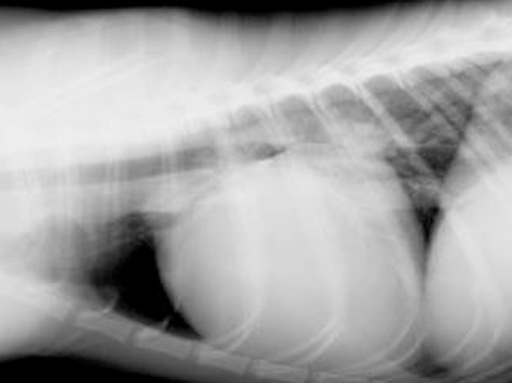

DDx

PPDH

: 복강 안 장기가 심낭 안으로 들어가 ⓐ 심장이 매우 커 보임.

- 선천성 질병이라 어릴 때 발생. (PE는 어릴 때 잘 X)

- ⓑ PPDH는 diaphragm silluette이 명확하지 않음.

- ⓒ 장에 차 있는 공기 음영이 보임